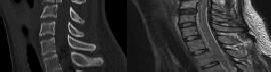

Preoperative MRI images are shown from a 67-year-old woman with neck pain, bilateral upper extremity paresthesias, progressively worsening balance, several falls, and increasing problems in both hands with dropping objects. Figure 1 is a sagittal view, Figure 2 is an axial cut at C2-3, Figure 3 is an axial cut at C5-6, and Figure 4 is an axial cut at C6-7. The patient’s motor strength is grade 4+ of 5 in the bilateral upper extremities.

What is the best next step?

4. Posterior decompression and fusion Discussion: D

The patient has degenerative changes with central and foraminal stenosis from C2-7, including spinal cord compression at C2-3, C5-6, and C6-7. Her progressively worsening balance, falls, and clumsiness are consistent with cervical spondylotic myelopathy. Given the progressive nature of the neurologic symptoms, surgery is recommended for patients with worsening

symptoms. Physical therapy potentially could provide pain relief but would not address the spinal cord compression. Cervical epidural steroid injection is not recommended because of the increased neurologic risk in the setting of substantial spinal cord compression. Given the multiple levels involved and the extension to the C2-3 level, an anterior approach would increase the risk of morbidity and pseudarthrosis compared with the posterior approach, which would allow adequate decompression of the central and foraminal stenosis.

Surgery for cervical myelopathy is performed to decompress the spinal cord, stabilize the spine, and prevent further neurologic injury. Most patients obtain considerable pain relief and some improvement in balance and clumsiness, depending on the severity of the symptoms. Complete resolution of all symptoms should not be expected.